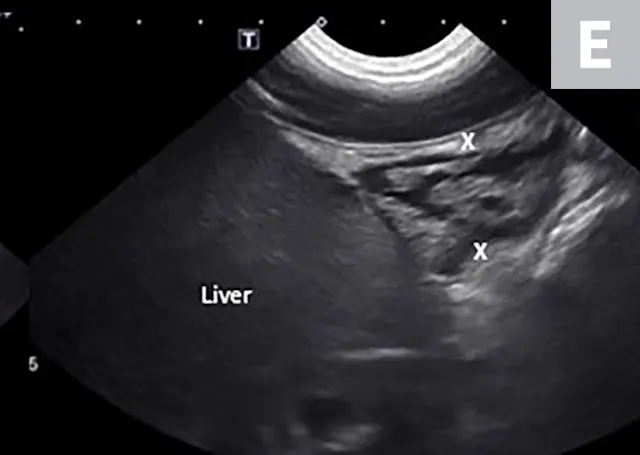

Imaging of a 1-year-old neutered male standard poodle presented with anorexia, lethargy, vomiting, hypoalbuminemia, hypoproteinemia, and cranial abdominal organomegaly. Transverse (A) and sagittal (B) ultrasound of the liver and gallbladder (GB). The liver is enlarged (with increased distance off the stomach from the diaphragm, rounded borders, and extension ventral to the stomach), diffusely hyperechoic, and homogenous. The gallbladder is moderately distended with a normal wall and content. Radiographs demonstrate hepatomegaly and splenomegaly (C). Abdominal ultrasound images revealed splenic enlargement with a mildly mottled architecture and a solitary hypoechoic nodule (D; arrowheads). The pancreas is enlarged and lobulated with multiple hypoechoic tracts and a peripheral capsule (E; between electronic cursors [X’s]). The jejunal lymph nodes are severely enlarged (F; between electronic cursors [X’s]), more than expected for a young dog. The combination of severe hepatosplenomegaly and lymphadenomegaly make systemic disease (eg, infectious, neoplastic) most likely. The appearance of the pancreas is due to pancreatic edema secondary to hypoproteinemia. Acute liver injury was diagnosed, and lymphoma was diagnosed based on hepatic and splenic cytology.